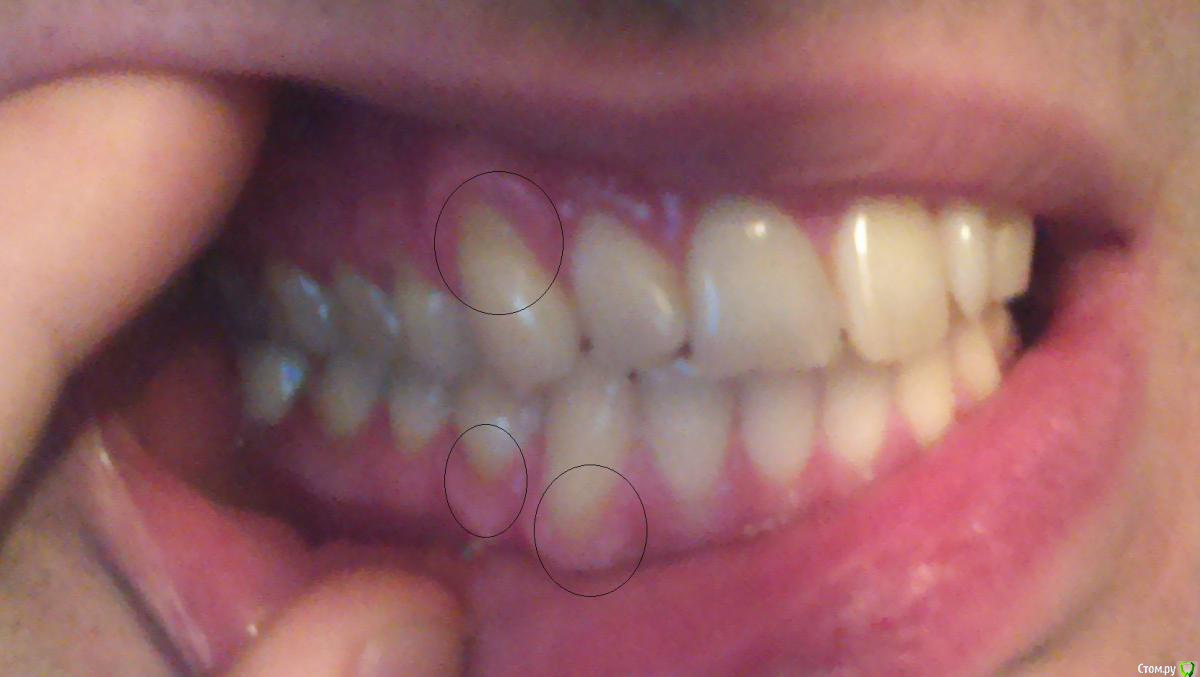

Bizzzin Опубликовано 7 декабря, 2015 Автор Поделиться Опубликовано 7 декабря, 2015 Конечно! В приложении направляю фотографии. Ссылка на комментарий

red_butler Опубликовано 8 декабря, 2015 Поделиться Опубликовано 8 декабря, 2015 Это рецессии десны, причина скорее всего в механической травме зубной щеткой. Закрываются они хирургическим путем. 3 Ссылка на комментарий